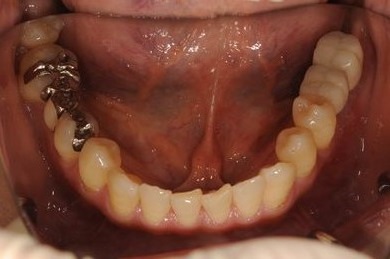

インプラントの症例写真 IMPLANT

インプラント治療

| 主訴 | 左奥歯のインプラント治療を希望。 | ||||||||||||||||||||||||||||||||

| 治療方針 | 左下奥、欠損部分をインプラント治療にて、機能的・審美的回復を行う。 | ||||||||||||||||||||||||||||||||

| 治療内容 | インプラント2本、ハイブリッドセラミッククラウン2本 | ||||||||||||||||||||||||||||||||

| 総治療費 | 399,000円 | ||||||||||||||||||||||||||||||||

| 治療期間 | 5ヶ月 |